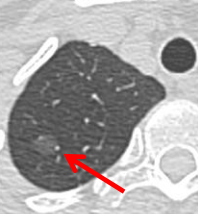

混合性磨玻璃结节

是指密度轻度增加,呈云雾状、结节状密度增高影,但病变密度又不足以掩盖其中走行的血管和支气管影。磨玻璃结节无实性成分称为纯磨玻璃结节(pGGN),含有实性成分称为混杂性磨玻璃结节(mGGN)。